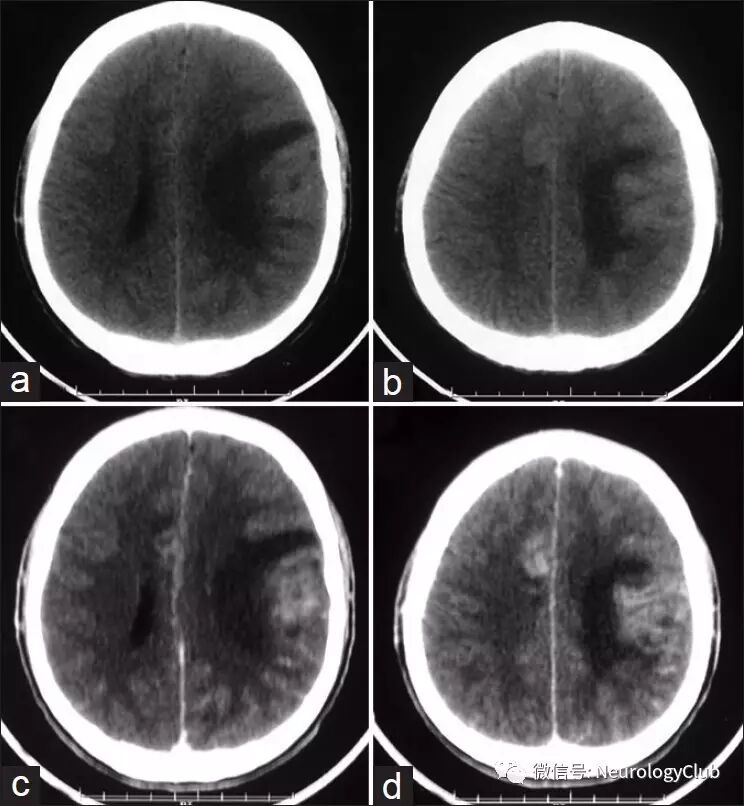

18岁男性,表现为进行性加重的左顶部疼痛逐渐发展为全头部疼痛27天,伴有恶心呕吐,右侧肢体渐进性轻偏瘫5天。无畏寒发热,无免疫缺陷及免疫抑制治疗的既往史。查体可见颈项强直,右侧轻偏瘫。脑脊液化验提示糖71mg/dL,蛋白132mg/dL,有核细胞20/dL(均为淋巴细胞),抗酸染色及细菌涂片阴性。CT及MR可见颅内多发病变伴强化(图1-2)。余常规实验室及影像学检查无殊。

(图1:CT平扫[a-b]和增强[c-d]可见左侧额顶叶边界不清的低密度病灶,右侧额上回线状脑回样强化)